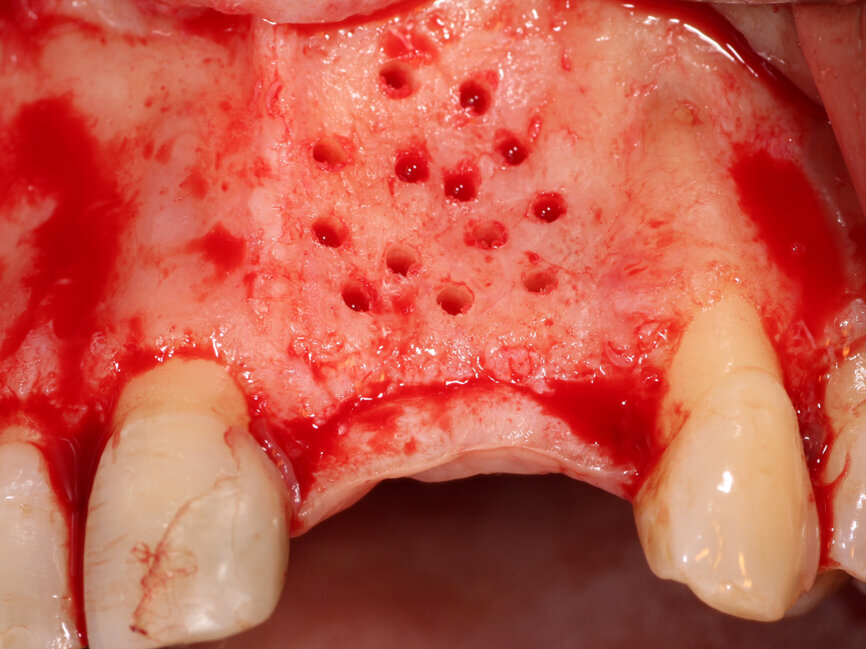

Fig. 4: The facial plate is fenestrated with a bur through the cortical bone in the edentulous space that will receive the osseous graft.

A #15 scalpel was utilized to create a vertical releasing incision between the right canine and lateral incisors and also between the left first and second premolars. These were connected by a facial sulcular incision medial to the vertical releasing incisions and a midcrestal incision at the edentulous area. A full thickness flap was elevated extending past the mucogingival junction to exposure the deficient area as well as bone covering the roots of the adjacent teeth (Fig. 3). A thin ridge with a notable concavity at the edentulous area was confirmed correlating with what was accessed on the CBCT exam. A three sided 1.2 mm bur from MedEquip Dental Supplies in a surgical handpiece was utilized to create multiple decortication points through the cortical bone to the underlying cancellous bone (Fig. 4). This is performed to allow endosteal osteoblasts from the cancellous bone to interact with the graft, grow bone around and within the particulate graft particle, and to accelerate vascularization of the graft and incorporation to the osseous bed.